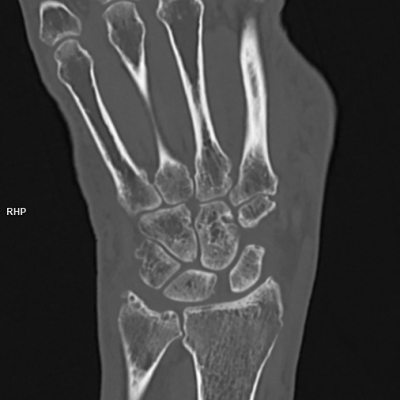

Vergleich konventionelles CT zu Photon-Counting-CT

Im medQuartier Feldkirchen setzen wir auf die modernste Technik und verwenden deswegen ein Photon-Counting-CT Gerät. In den folgenden Bildvergleichen sehen Sie links jeweils eine Aufnahme aus einem konventionellen CT, rechts jene aus einem PCCT. Die deutlich höhere Bildauflösung bei gleichzeitig wesentlich geringerer Strahlenbelastung ist klar erkennbar. Besonders profitieren davon Kinder sowie Patientinnen und Patienten mit regelmäßig notwendigen Kontrolluntersuchungen.

Der Vergleich eines konventionellen CTs mit einem Photon-Counting-CT entspricht in etwa einem Vergleich von einem pixeligen „Schwarzweiß Röhrenfernseher“ zu einem „hochmodernen 8K Flatscreen“.

Handgelenk

Beim Gelenken sind mit dem Photon-Counting-CT Darstellungen von feinsten Strukturen möglich.